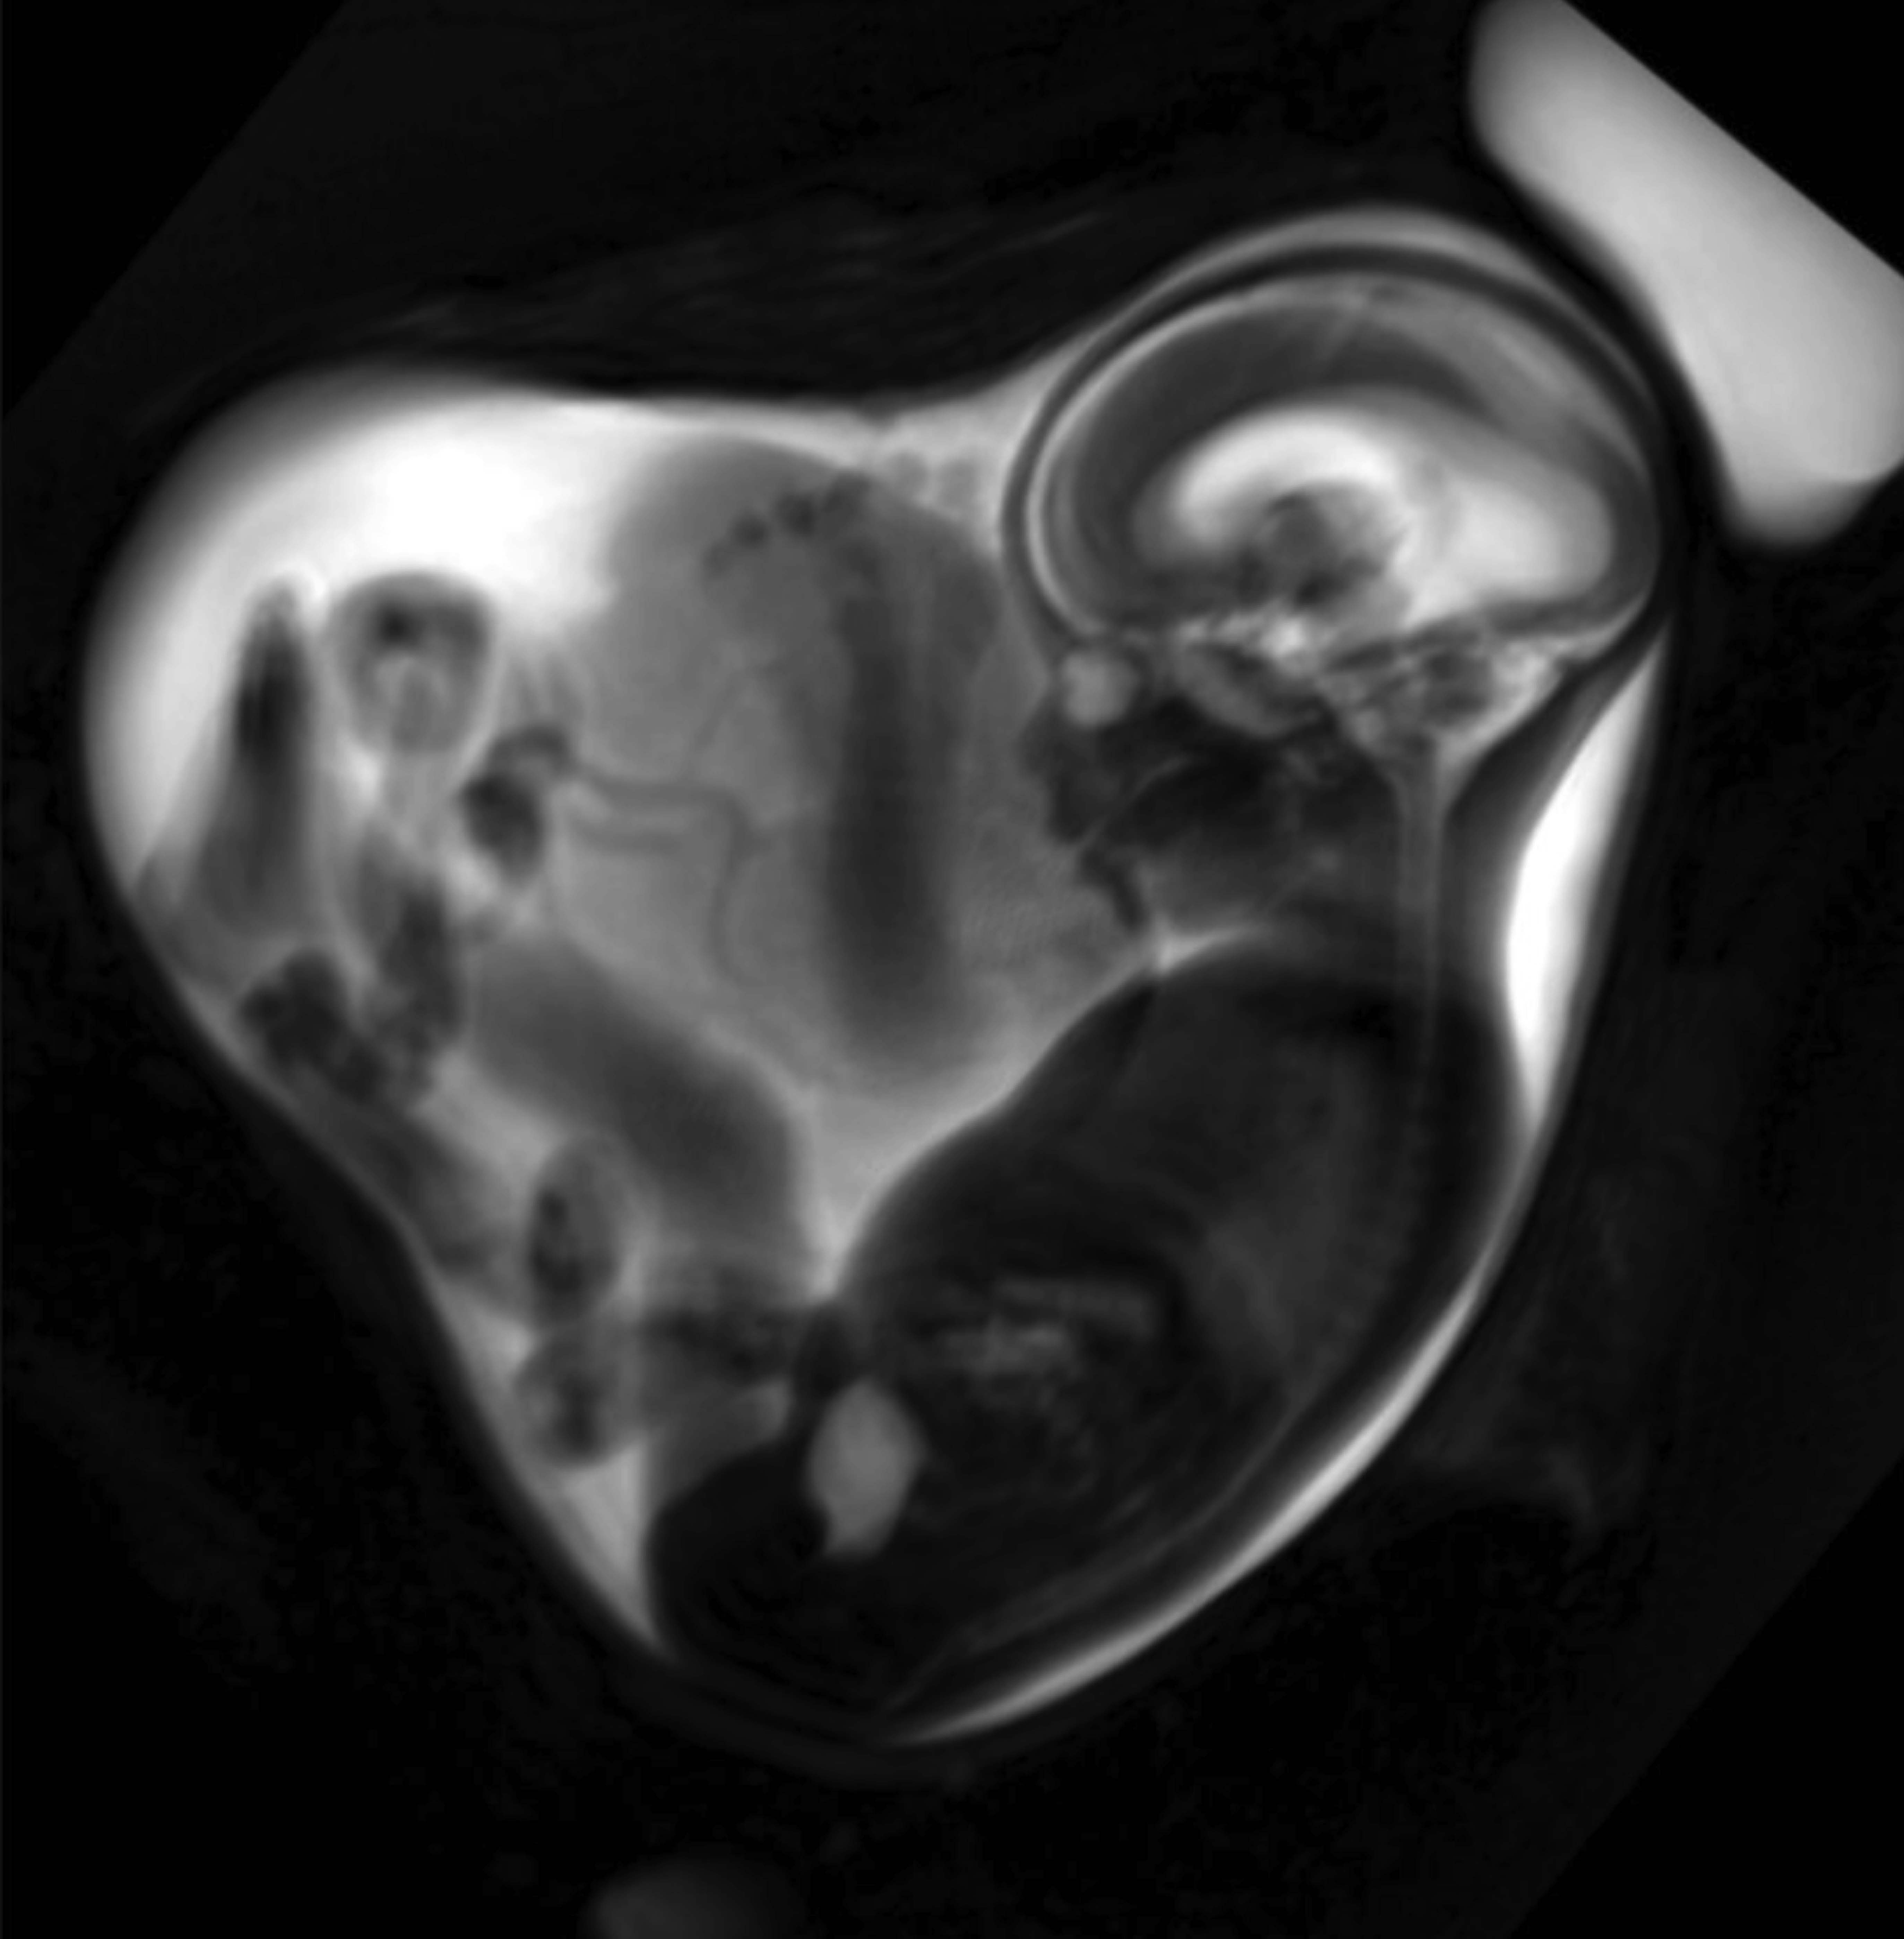

Die Forschenden um Prof. Dr. Sophia Stöcklein von der Klinik und Poliklinik für Radiologie des LMU Klinikums und Privat-Dozentin Dr. Anne Hilgendorff vom Zentrum für Comprehensive Developmental Care des LMU Klinikums und von Helmholtz Munich haben insgesamt 34 Schwangere respektive Feten mittels fetaler MRT untersucht. Die fetale MRT ist eine hochspezialisierte Untersuchungsmethode, die es ermöglicht, die Entwicklung fetaler Strukturen bereits vor Geburt detailliert zu untersuchen. Die Frauen hatten sich zu unterschiedlichen Zeitpunkten mit der Alpha-Variante des Corona-Virus infiziert, bestätigt durch PCR-Test. Die Lungen der Feten wurden mittels Magnetresonanz-Tomografie vermessen, das Lungenvolumen bestimmt und mit Feten aus einer sogenannten Referenzkohorte verglichen, bei denen keine Infektion während der Schwangerschaft stattgefunden hatte.

„Die Feten von Schwangeren, die positiv auf SARS-CoV-2 getestet waren, hatten insgesamt ein im Vergleich zur Referenzkohorte geringeres Lungenvolumen“, erklärt Sophia Stöcklein. Bei den Feten im dritten Trimenon war der Effekt besonders deutlich, mit durchschnittlich 69 Prozent des zu erwartenden Durchschnittswerts bei normaler Lungenentwicklung.